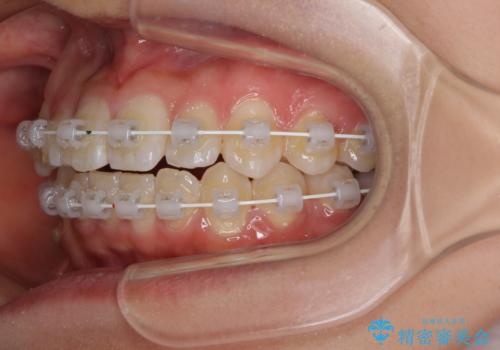

- 審美装置

- 上下のデコボコと前歯のクロスバイトを改善したいとのことで来院された患者様です。

極力短期間で治療したいとのことで、ワイヤー装置による矯正治療を行うこととしました。

お住まいが遠方であったため、マウスピースによる矯正治療も提案しましたが、ご自身でのマウスピースの管理の面倒くささと、なるべく早く治療を終えたいとのことで、ワイヤー矯正を選択されました。